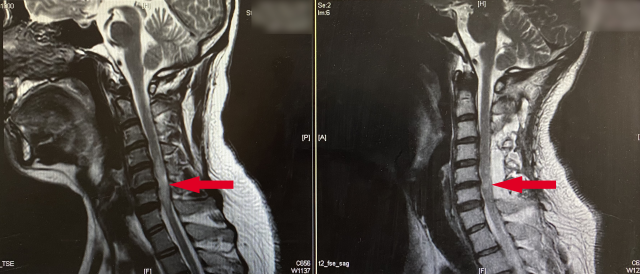

图为手术前后的核磁影像对比

核磁影像上颈髓内的异常信号是影响决策的关键。“多种原因导致的脊髓炎症和脊髓恶性肿瘤,在核磁影像上很难区分。”章薇说,而通过手术活检,进行病理确诊,更面临着损伤颈髓的风险,将直接导致患者在活检术后出现运动、感觉的功能障碍,严重影响生活质量。

经过充分的沟通,最终,小晨和父母接受了手术治疗,并选择了解决椎管狭窄的手术方案。手术由王劲、章薇联合主刀,为小晨进行了“颈椎管解压与椎管扩大成形术”,即通过切开棘突和椎板复合物打开狭窄的椎管,将该复合物用人工材料原位架高后固定,目的是治疗因颈椎管狭窄所致的脊髓损伤。术后7天复查核磁,颈髓内异常信号连同颈椎弧度较术前都有显著改善。小晨已开始锻炼重新走路,将于近日出院。